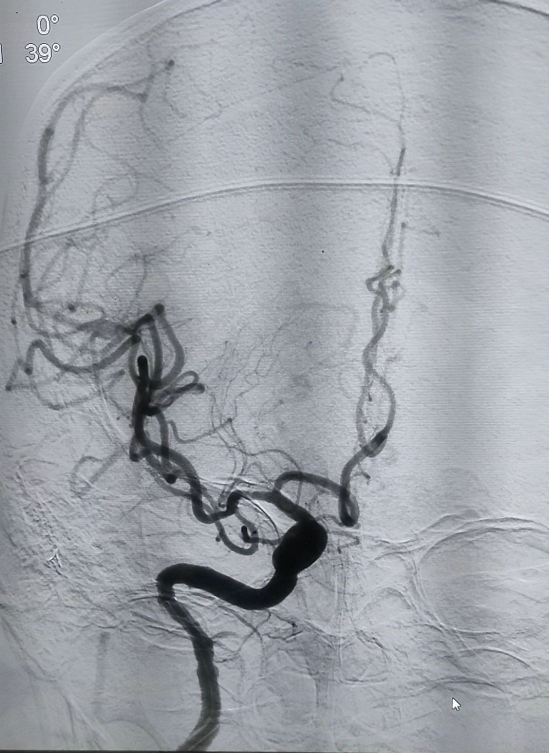

征得家属同意后,医疗团队立即为患者行脑血管造影,检查发现存在患者右侧大脑中动脉急性闭塞。明确责任血管后,微导丝超选到位,释放支架取栓,经过一个多小时的奋战,成功取出堵塞血管的血栓,较大者约6mm,实现大脑中动脉的再通,造影复查,右侧大脑中动脉显影通畅,mTICI分级:3级。撤出导管,血管缝合器缝合血管后,按压穿刺点20分钟无渗血后包扎。经过2个小时的“生死接力”,手术成功完成,患者随即脱离了生命危险,得到了病人家属高度认可和满意。

▲图为颅内血管显影,血管再通